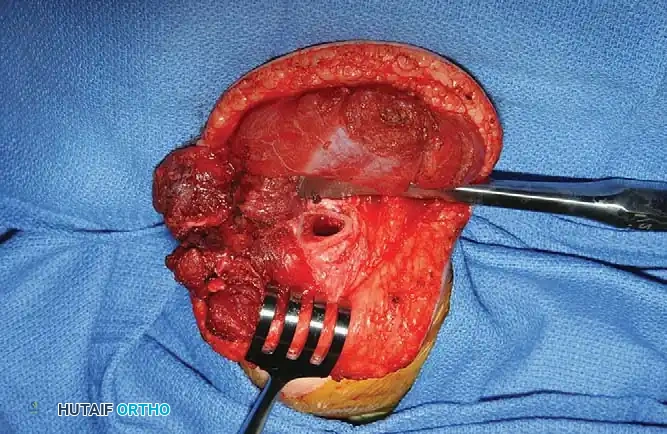

Surgical Technique: The Menelaus Procedure

The procedure requires meticulous soft tissue handling, extensive mobilization of the triceps muscle belly, and careful protection of the ulnar nerve.

Step 1: Exposure and Tendon Harvest

* Position the patient in the lateral decubitus or supine position with the arm draped free over a sterile bolster. Use a sterile tourniquet to optimize the surgical field.

* Make an extensile lateral incision to expose the distal aspect of the triceps muscle, continuing distally to expose the anterior, lateral, and posterior aspects of the proximal ulna.

* Identify the broad triceps insertion on the olecranon.

* Dissect a robust, V-shaped "tongue" of periosteum from the proximal end of the ulna, maintaining its continuity with the distal triceps tendon. This periosteal extension is critical for providing adequate length and a durable tissue interface for the subsequent osseous fixation.

Step 2: Muscle Mobilization and Nerve Protection

* Proceed with proximal dissection of the triceps muscle belly up to the midarm level. Free the muscle from its fascial attachments to the intermuscular septa to ensure maximum excursion.

* Identify, neurolyse, and mobilize the ulnar nerve. The nerve must be protected throughout the procedure, as the proximal mobilization of the triceps can place it under significant traction.

* Perform a posterior capsulotomy of the elbow joint to facilitate unimpeded flexion and to allow the transferred tendon to glide smoothly anteriorly.

Step 3: Tendon Routing and Fixation

* Tubularize (roll) the periosteal tongue and the distal triceps tendon using a running locking suture (e.g., #1 or #2 nonabsorbable braided suture) to create a strong, cylindrical graft.

* Identify the coronoid process of the ulna anteriorly. Using a drill and curettes, create a transosseous tunnel through the coronoid process.

* Pass the tubularized triceps tendon through the coronoid tunnel from anterior to posterior.